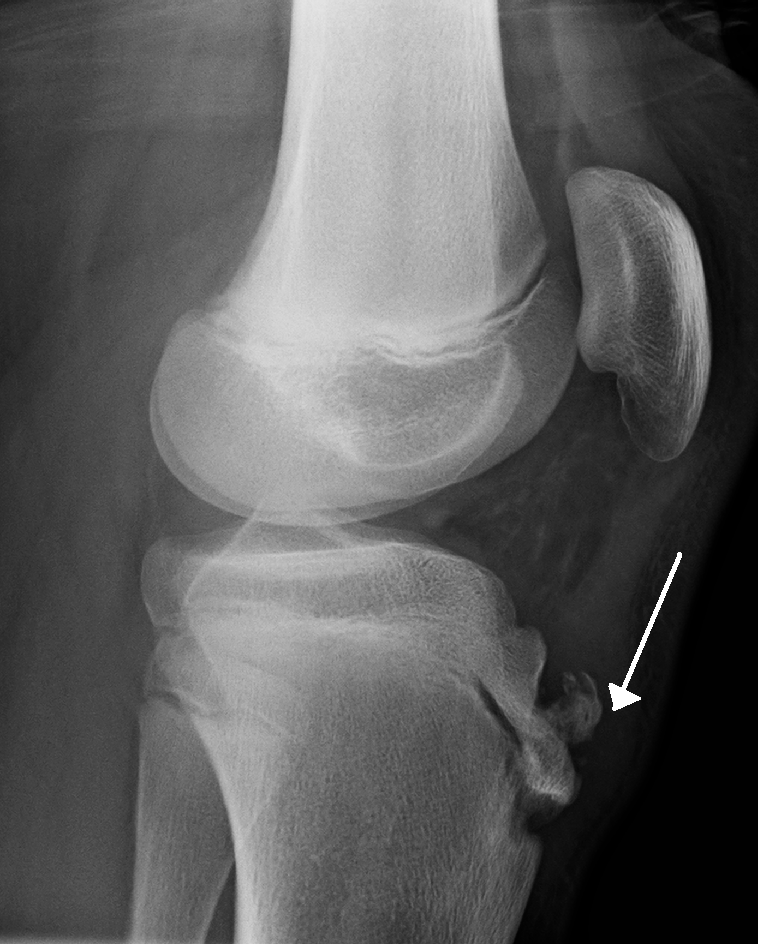

Gender: Male. x-ray. Symptomatic right knee: Fragmented apophysis at tibial tuberosity. Overlying soft tissue swelling is noted. Soft tissue haziness is noted in inferior most part of fat pad; obliterating shadow of inferior most part of patellar ligament. Asymptomatic left knee: No fragmented apophysis at tibial tuberosity.. 3.1 X-Ray. Radiological findings in Osgood-Schlatter disease depend on the severity of disease and differ during the acute and chronic phases. A typical appearance on a radiograph during the acute phase is blurring of the margins of the patellar tendon due to soft tissue swelling. Thickening of the ligamentum patellae can also sometimes be seen.

Osgood-Schlatter Disease; Other names: Apophysitis of the tibial tubercle, Lannelongue's disease, osteochondrosis of the tibial tubercle: Lateral view X-ray of the knee demonstrating fragmentation of the tibial tubercle with overlying soft tissue swelling.: Specialty: Orthopedics: Symptoms: Painful bump just below the knee, worse with activity and better with rest. In addition to a complete medical history and physical examination, diagnostic procedures for Osgood-Schlatter disease may include: X-rays. A diagnostic test that uses invisible electromagnetic energy beams to produce images of internal tissues, bones, and organs onto film. X-rays may be performed to rule out other lesions.